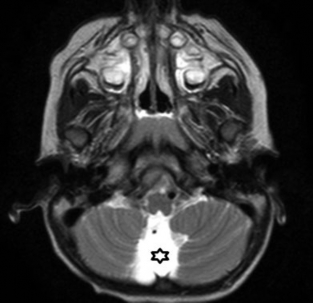

Es la dilatación marcada de la cisterna magna generando ensanchamiento de la fosa posterior, no acompañada de alteraciones cerebelosas (►Fig. 8).11 La megacisterna puede presentar expansión posterior, inferior o lateral y es atravesada por vasos venosos innominados, tributarios del seno longitudinal inferior.11 El diagnóstico diferencial debe realizarse con:11

(A-B) TC, corte axial de cerebro (A). Aumento del diámetro de la cisterna Magna (*). Nótese la presencia de estructuras vasculares venosas en su interior (flecha). RM, cortes sagital axial ponderado en T2 (B) se objetiva aumento de los diámetros de la cisterna Magna (*) atravesada por estructuras vasculares (flecha).